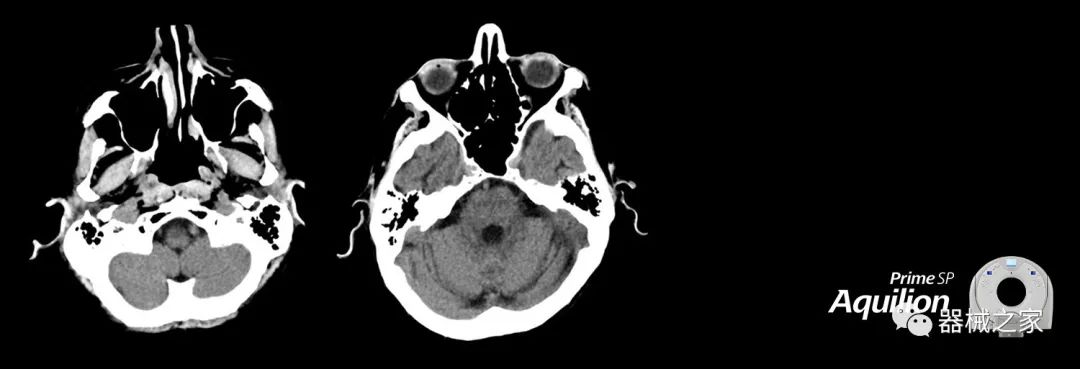

在以患者為中心的放射腫瘤學(xué)領(lǐng)域,計算機斷層掃描(CT)的可訪問性,可重復(fù)性和靈活性至關(guān)重要。為了建立這些價值,佳能醫(yī)療系統(tǒng)美國公司現(xiàn)在正在擴大其放射腫瘤學(xué)CT模擬產(chǎn)品,包括Aquilion Prime SP和Aquilion Lightning 80高級CT系統(tǒng)。除了Aquilion LB之外,Aquilion Prime SP和Aquilion Lightning 80現(xiàn)在還包括放射治療(RT)選項,可為腫瘤學(xué)規(guī)劃提供高質(zhì)量的CT成像和精密工具。

擴展視野(EFOV)可以看到更多的解剖結(jié)構(gòu)。Aquilion LB采用85 cm EFOV,而Aquilion Prime SP和Aquilion Lightning 70采用70 cm EFOV。

Aquilion Prime SP使設(shè)施能夠處理具有挑戰(zhàn)性的案例,同時為員工提供快速,靈活和高效的解決方案。

佳能醫(yī)療的Aquilion Lightning 80掃描儀還以緊湊,經(jīng)濟的包裝提供高質(zhì)量的成像。Aquilion Lightning 80旨在可靠,高效地運行,在繁忙的環(huán)境中生成高質(zhì)量的圖像。

兩個CT系統(tǒng)均采用0.5 mm x 80排PUREViSION探測器技術(shù)(可配置并從80-160現(xiàn)場升級),78 cm孔徑,50 cm視野,AIDR(自適應(yīng)迭代劑量減少)3-D和SEMAR(單個)能量金屬神器減少)技術(shù)。

Aquilion LB專為滿足腫瘤學(xué)挑戰(zhàn)而設(shè)計,同時優(yōu)先考慮患者護理。Aquilion LB的內(nèi)徑為90 cm,能夠幫助復(fù)雜的患者設(shè)置并提高患者的舒適度。CT模擬定位可以輕松鏡像放射治療定位,更加自信。該系統(tǒng)采用0.5 mm x 16排(32層)PUREViSION探測器技術(shù),70 cm視野,AIDR 3D和SEMAR技術(shù)。